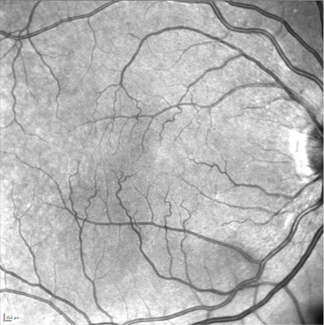

Image Infrarouge 35° : œil droit avec rétine sans anomalie